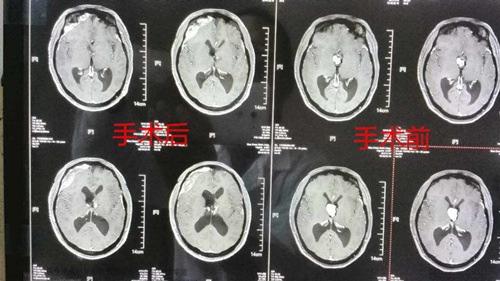

术后术前CT影像资料对比:肿瘤切除得十分干净

术后两次复查头颅CT示:肿瘤切除干净。第三、四天,患者精神症状消失,意识清醒,回答问题清楚,见人也会主动打招呼,更没有出现术前担心的意识障碍、偏瘫、多饮多尿等症状。和术前打针、剃头、导尿等不配合,躁动起来几个人都按不住,更在术前剃头时扬言:“谁要剃我的头,我就要先把谁的头给剃了”已判若两人。